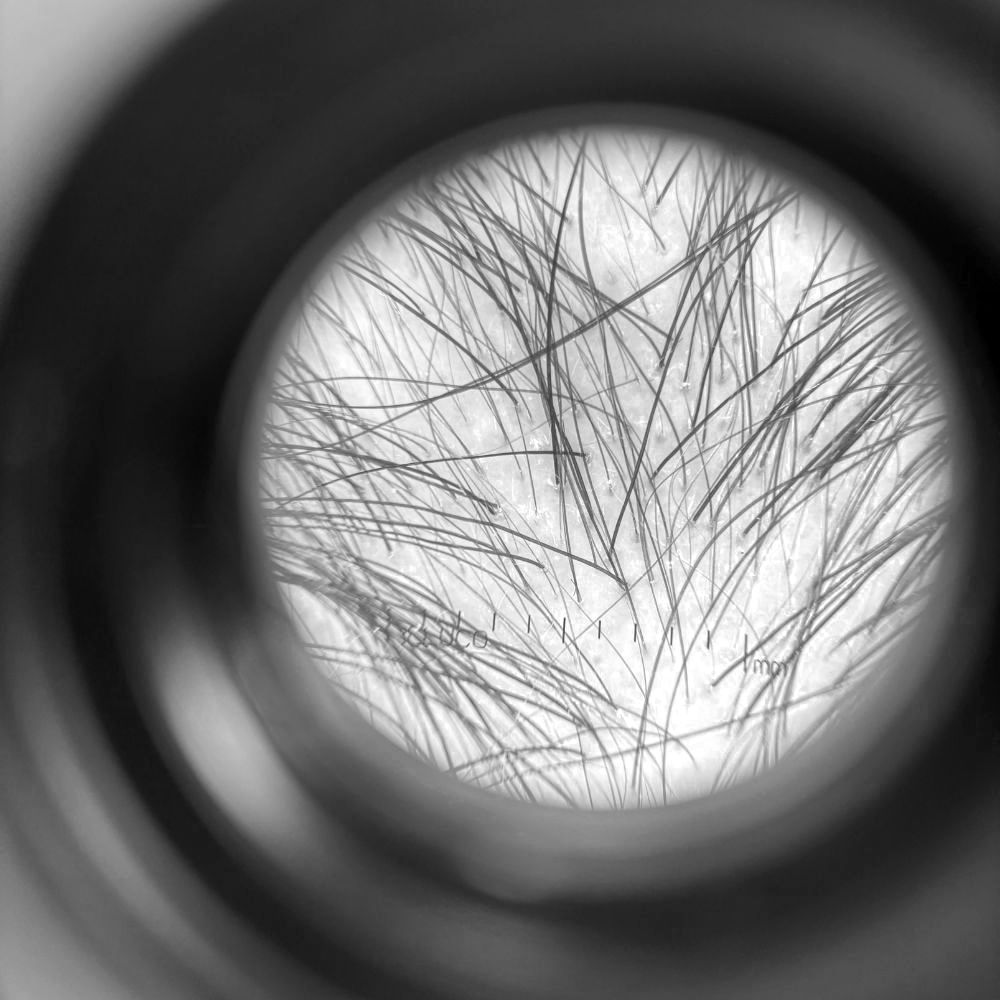

tricologia

Ogni percorso inizia dall’ascolto e da una valutazione medica accurata. Attraverso un approccio rigenerativo e personalizzato, individuo la terapia adatta per viso, corpo e capelli, con l’obiettivo di migliorare l’equilibrio, il benessere e la naturalezza nel tempo.